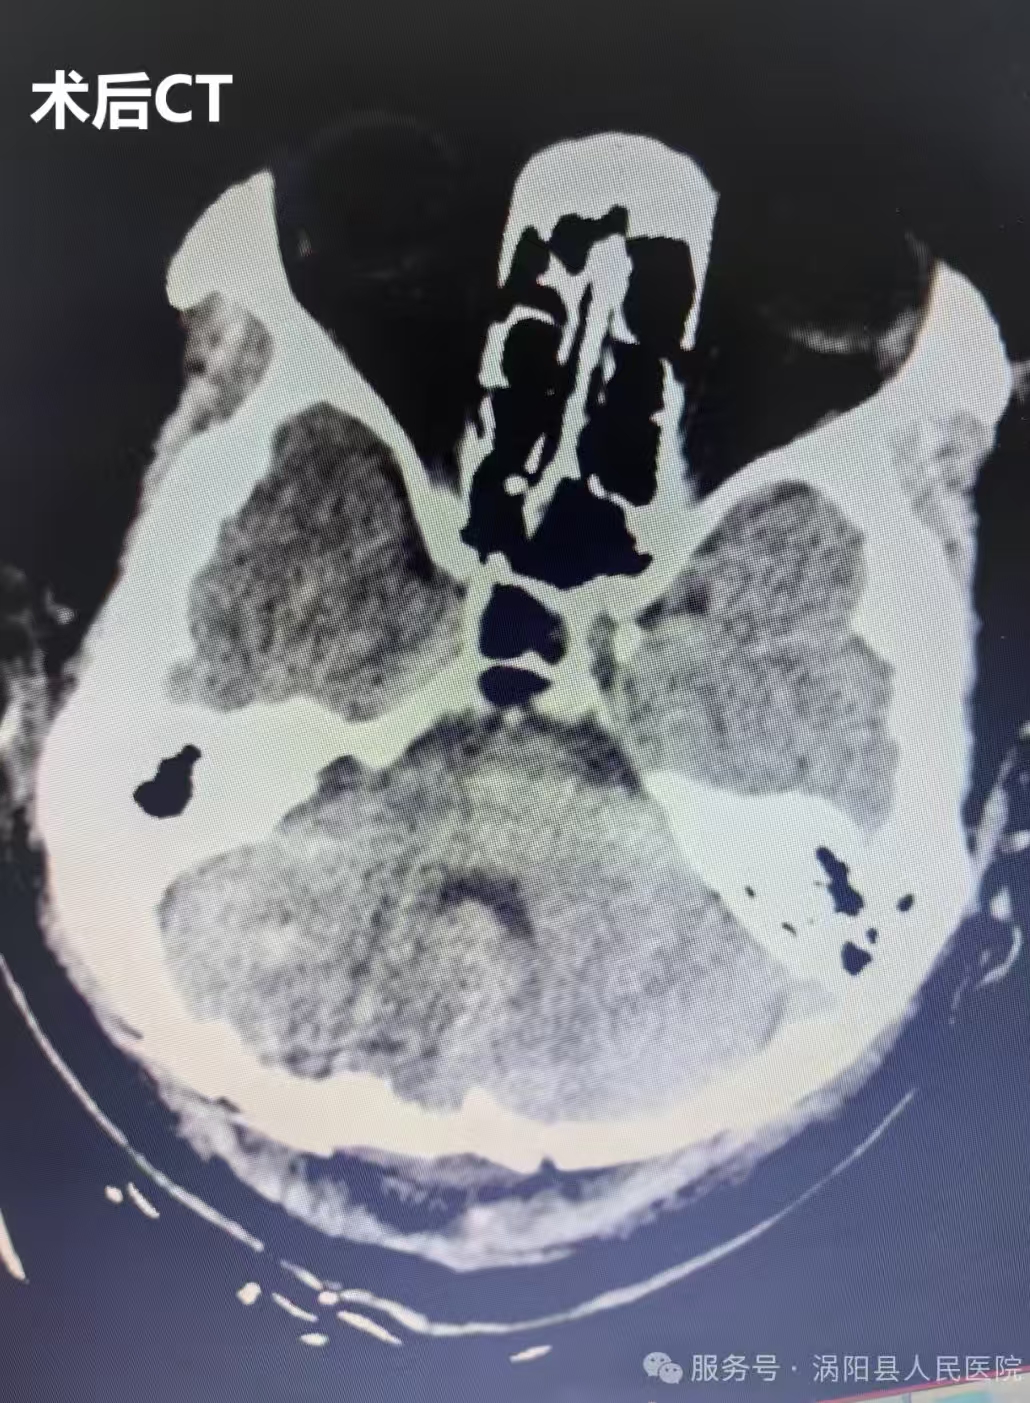

3月13日,手术正式开展。在全身麻醉下,由神经外科主任医师周维广、王超领衔的手术团队,在手术显微镜下精准施治。该手术采用后正中入路,手术视野深、操作空间狭小,对主刀医生的心理素质和专业技术都是极大考验。手术团队凭借丰富的临床经验、娴熟的显微外科技术,历经6小时细致操作,成功完整切除病变组织,并将标本送检病理检查。术后复查CT显示,手术效果理想,患者颅内情况良好。